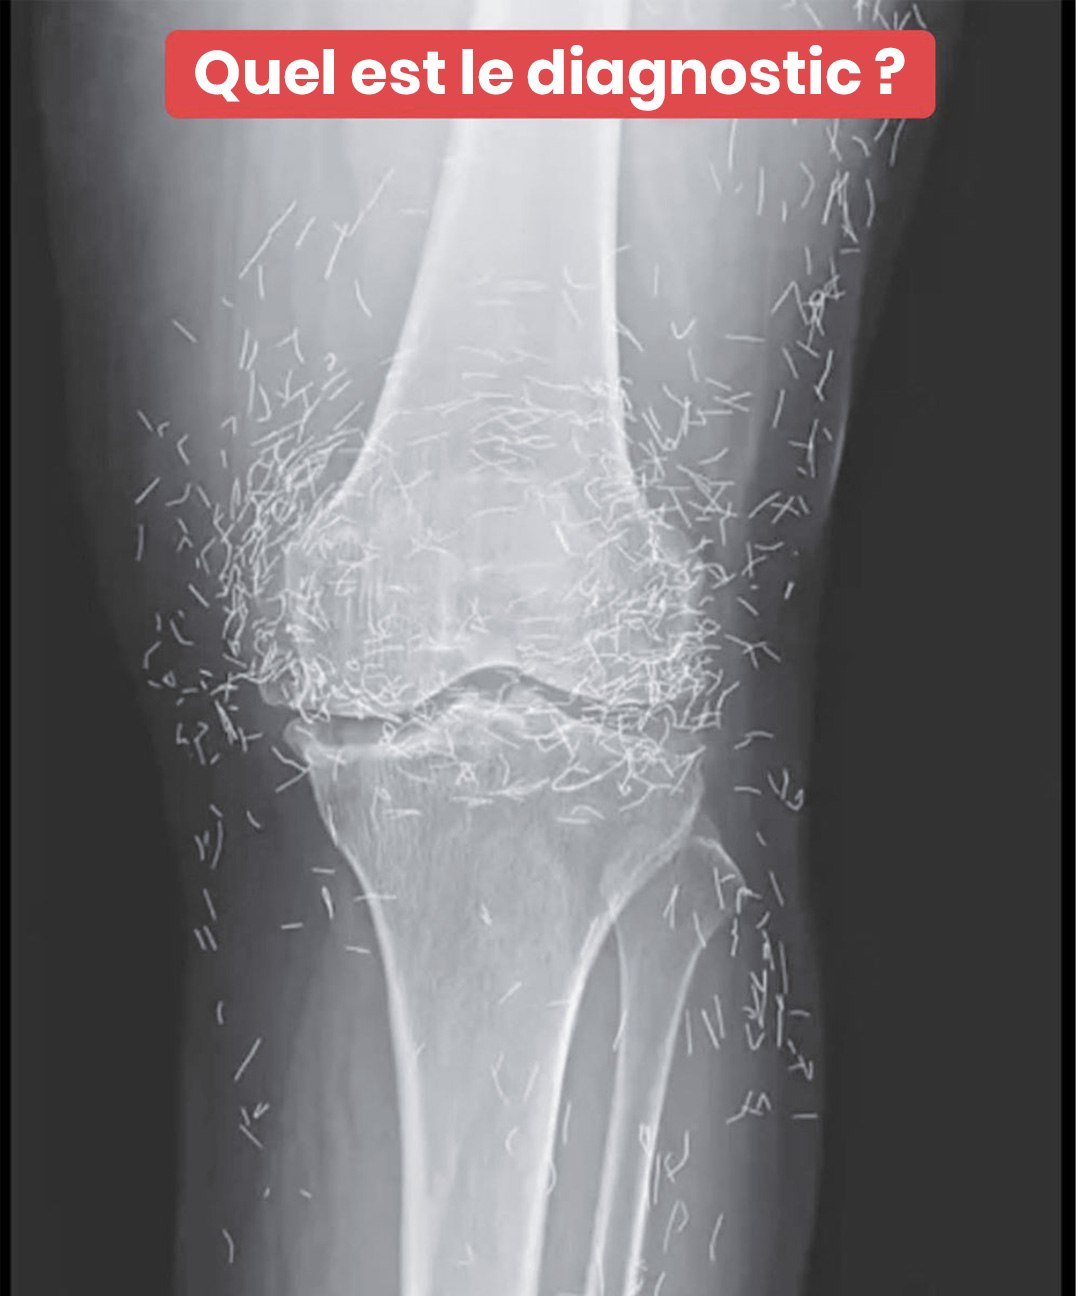

Imaginez passer une simple radiographie pour des douleurs aux genoux… et découvrir que votre corps renferme un véritable trésor caché ! C’est ce qui est arrivé à une femme de 65 ans, dont les clichés médicaux ont révélé une présence pour le moins inattendue. Ce que les médecins ont vu a soulevé bien plus de questions qu’il n’a apporté de réponses. Et derrière cette image intrigante se cache une pratique encore relativement méconnue en France, pourtant largement utilisée à travers le monde…

À ce stade, elle s’est tournée vers une alternative bien connue en Asie : l’acupuncture. Mais pas n’importe laquelle…